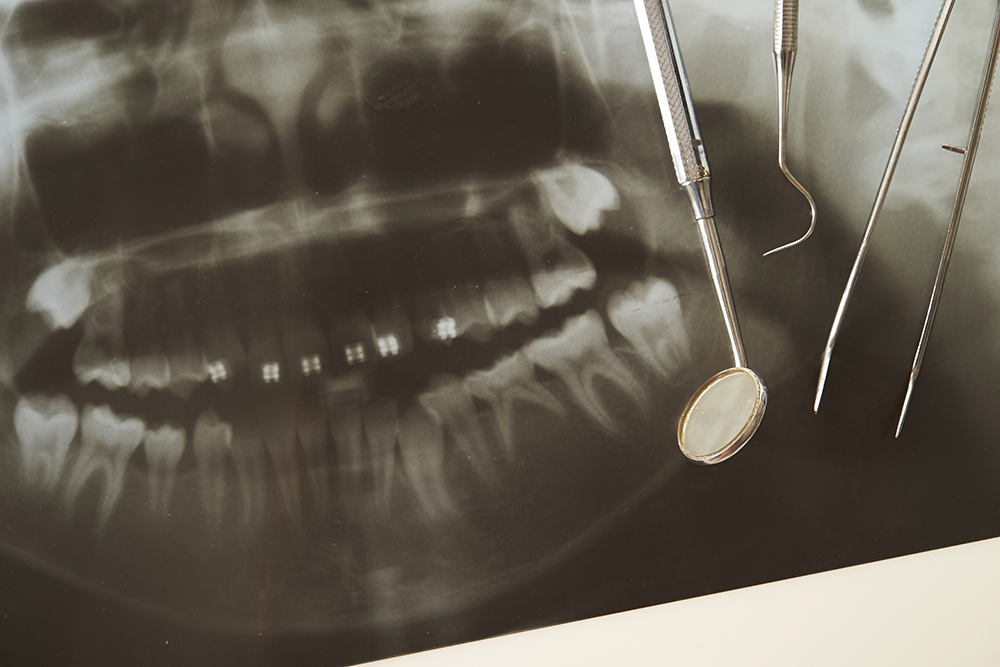

当院の方針は、歯をなるべく抜かずに治療することです。患者さんの本来の歯を活かして快適な生活を送っていただけるよう、さまざまな知識、技術、方法をもって治療にあたります。

虫歯や歯周病にならないためにも日頃のセルフケアなどが重要となります。生活習慣や食生活、きちんとした歯のブラッシングなど、ストレスを感じないようなライフスタイルと歯のセルフケアをしっかりとできていれば虫歯や歯周病になる可能性は低くなります。